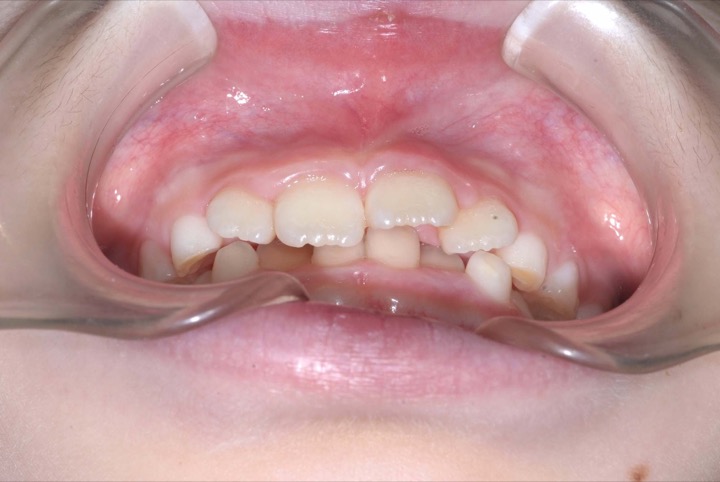

初診時年齢9才の女子で上下顎前歯の部の乱ぐいを気にして来院されました。

検査の結果、叢生と過蓋咬合を伴うアングルⅠ級不正咬合と診断しました。